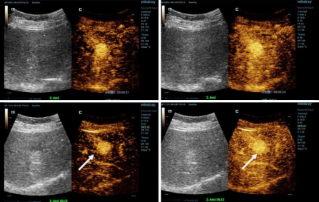

![Des diagnostics plus précis avec l’HiFR CEUS]() Des diagnostics plus précis avec l’HiFR CEUSL'échographie de contraste (CEUS) est un domaine très dynamique et, au cours des dernières années, les innovations technologiques ont encore permis d'améliorer la qualité des images. L'une de ces innovations est l'échographie de contraste améliorée à haute cadence images (HiFR CEUS), en mesure de générer jusqu'à dix fois plus d'images que l'échographie conventionnelle dans le même intervalle de temps.Ultrasound | Imagerie générale 2022-12-16

Des diagnostics plus précis avec l’HiFR CEUSL'échographie de contraste (CEUS) est un domaine très dynamique et, au cours des dernières années, les innovations technologiques ont encore permis d'améliorer la qualité des images. L'une de ces innovations est l'échographie de contraste améliorée à haute cadence images (HiFR CEUS), en mesure de générer jusqu'à dix fois plus d'images que l'échographie conventionnelle dans le même intervalle de temps.Ultrasound | Imagerie générale 2022-12-16 -